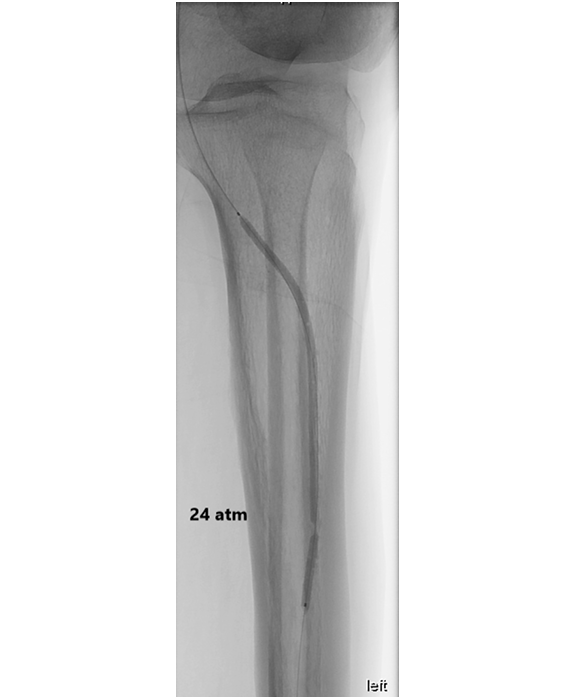

钙化斑块的病理类型分为内膜性钙化(常见于动脉粥样硬化晚期,呈片状或结节状)、中膜性钙化(Mönckeberg硬化,多见于糖尿病和慢性肾病,呈环形、连续状)以及混合型。其中,中膜环形钙化对球囊扩张的抵抗最强,因为其钙化层位于平滑肌层外,球囊压力无法有效撕裂该结构。常规高压球囊(额定爆破压20-24 atm)在遇到360°中膜钙化时,常常出现“狗骨征”(dog-boning)或局部夹层,而管腔获得极小。斑块旋切设备(如TurboHawk、JetStream)对浅表内膜钙化有效,但对深层或环形中膜钙化效果有限,且有远端栓塞和穿孔风险。血管内碎石(Intravascular Lithotripsy, IVL)通过冲击波选择性作用于钙化,对中膜钙化有效,但设备昂贵、球囊尺寸限制(目前最小IVL球囊直径为2.5mm,如Shockwave M5+,适用于2.5-4.0mm血管,仍无法用于更细的踝下动脉如足背动脉直径1.5-2.5mm)。

压裂技术采用经皮置入18G针至钙化斑块内,球囊加压注射液压,压力骤降提示钙化断裂。具体操作步骤为:在常规球囊扩张失败后(残余狭窄>50%或IVUS示MLA<12mm²),保留导丝和微导管;更换为8F或9F长鞘增加支撑力;将18G穿刺针(外径1.3mm,内径约0.9mm)经皮穿刺,在双平面透视或IVUS引导下,针尖指向钙化最厚处(IVUS表现为高回声伴声影,钙化厚度>1mm);确认针尖位于钙化斑块内后撤出针芯,连接高压注射器或手动压力泵;选择与血管直径匹配的半顺应性或非顺应性球囊(通常直径5-7mm用于CFA),置于针尖所在节段,以4-6 atm低压扩张,使球囊紧贴血管壁;通过针腔缓慢注射生理盐水(或50%造影剂混合液),同时监测注射压力和球囊压力,当注射压力达到300-400 psi(约20-28 atm)时通常会突然下降50-100 psi,同时球囊压力曲线出现“凹陷”或“抖动”,提示钙化断裂;立即停止注射,撤出针,用球囊充分扩张(10-20 atm,持续30-60秒),IVUS复查证实MLA显著增大;根据残余狭窄和夹层情况决定是否植入支架或仅使用药物涂层球囊。